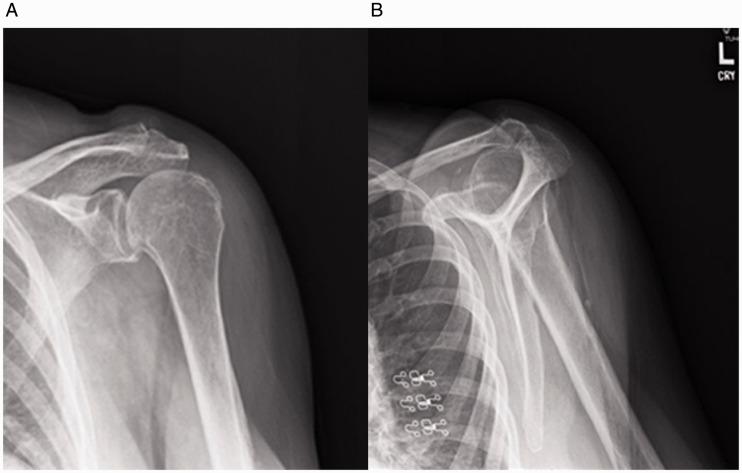

Reverse shoulder arthroplasty is a useful procedure with broadening applications, but it has the best outcomes when used for rotator cuff tear arthropathy. However, this procedure is not without complications. While scapular notching and aseptic loosening are more common complications that have been extensively studied in the literature, dissociation of the glenoid component and incomplete glenosphere seating has not received much attention. Specifically, little research has explored appropriate management of incomplete seating of the glenosphere component, and no gold standard for treatment of this complication has emerged. In the case described here, an elderly patient with an incompletely seated glenosphere component post-operatively opted to pursue conservative management in order to avoid revision surgery if possible. The partially engaged, superiorly directed components in this case exhibited spontaneous complete and symmetric seating of the glenosphere between six and twelve months post-operatively, indicating that conservative management of this complication in low-demand patients may be a viable option to avoid the risks associated with revision surgery. Further research should be pursued to explore what patient and prosthesis design factors may be suited to observation with serial radiographs when incomplete seating of the glenosphere component occurs.

反肩关节置换术是一种应用日益广泛的有效手术,但用于肩袖撕裂性关节病时效果最佳。然而,该手术并非没有并发症。虽然肩胛切迹和无菌性松动是文献中已广泛研究的较常见并发症,但关节盂组件分离和关节盂球窝不完全就位并未受到太多关注。具体而言,很少有研究探讨关节盂球窝组件不完全就位的适当处理方法,且尚未出现治疗该并发症的金标准。在此所述病例中,一名老年患者术后关节盂球窝组件就位不完全,为尽可能避免翻修手术,选择采取保守治疗。该病例中部分嵌入、向上指向的组件在术后6至12个月内关节盂球窝自发完全且对称就位,表明对需求较低的患者的这种并发症采取保守治疗可能是避免翻修手术相关风险的可行选择。应进一步开展研究,以探索当关节盂球窝组件不完全就位时,哪些患者和假体设计因素可能适合通过系列X线片进行观察。